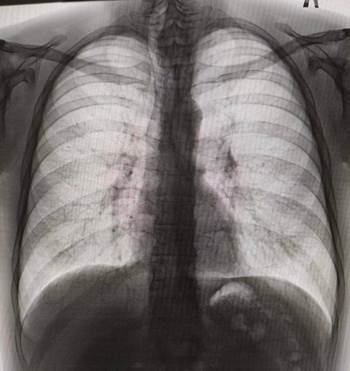

Рис. 1. Рентгенограмма органов грудной клетки. Составлено авторами по результатам рентгенологического исследования пациента

Рентгенография органов грудной клетки. Заключение. Усиление, деформация легочного рисунка, преимущественно в прикорневых зонах обоих легких. Некоторое расширение сердечной тени. Трахея несколько смещена вправо (рис. 1).